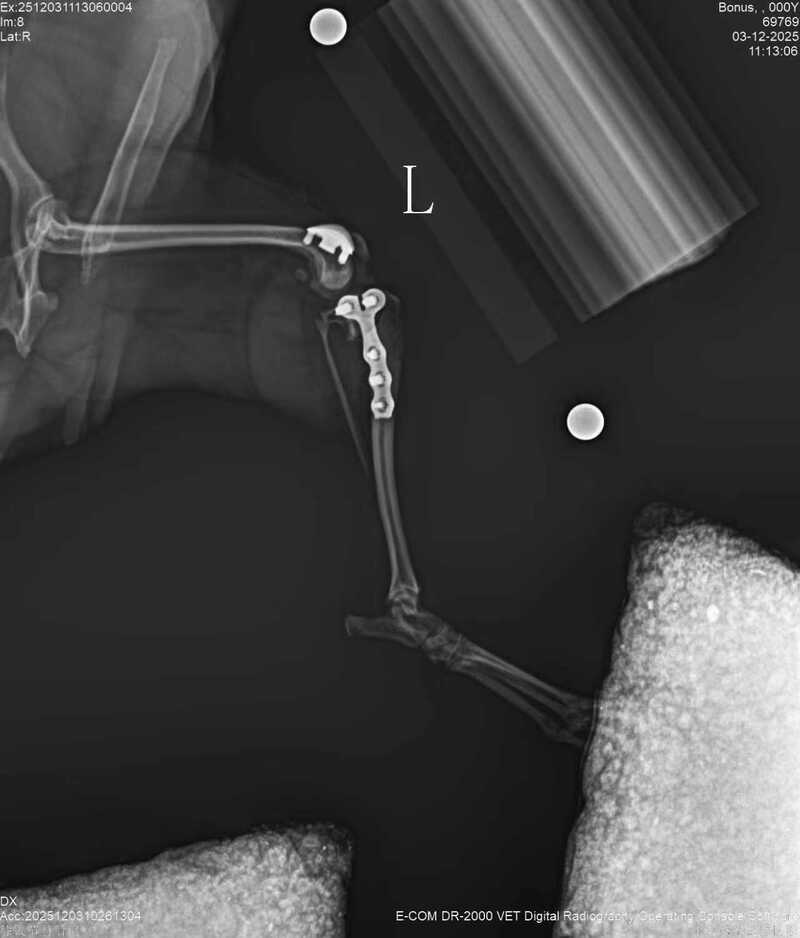

One week ago, the dog suddenly developed left hind limb lameness. The anterior cruciate ligament was ruptured and bilateral patellar dislocation occurred. A bilateral trochlear groove replacement and TPLO surgery was decided to be performed.

During the operation, the BlueSAO biologicalPGRSystem #1 implant was used for replacement, and the BlueSAOTPLO-5 mm L pure titanium locking plate was used for internal fixation. The surgery caused minimal damage and the recovery would be faster. The dog could bear weight and walk 3 days after the surgery. Hope for a speedy recovery.